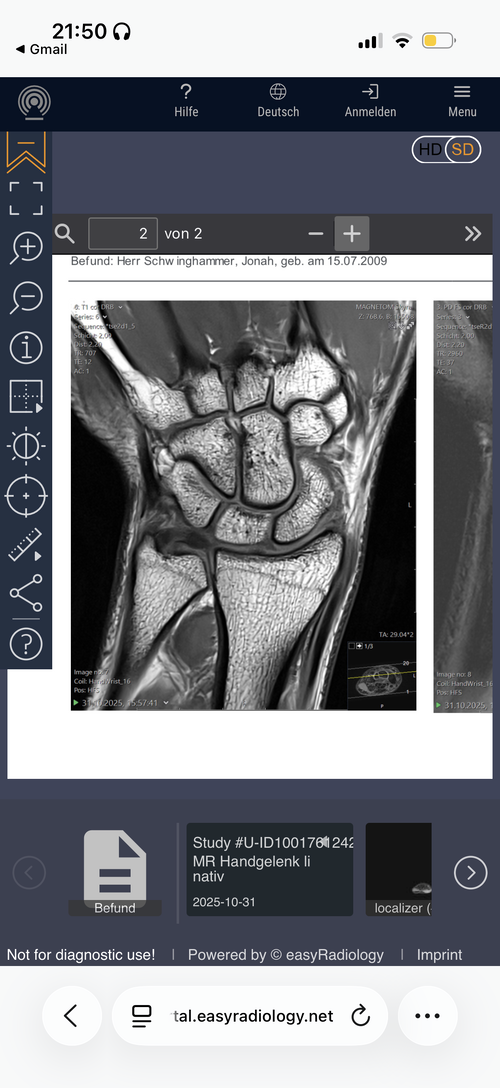

Are my growth plates closed and if not how much growth would hgh + ai help me grow?

Attachments

• IMG_0429.png

IMG_0429.png

Your hands won’t grow, this dosent mean your legs growth plates are closed tho.